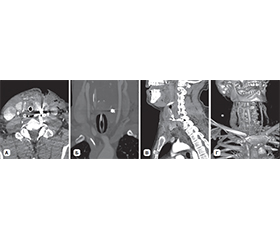

Актуальність. У статті проведений аналіз обстеження та лікування вогнепальних поранень шиї з ушкодженням щитоподібної залози (ЩЗ) за останні три роки в умовах Військово-медичного клінічного центру Північного регіону КМС ЗСУ. Мета: розробка та впровадження класифікації вогнепальних поранень шиї з ушкодженням ЩЗ. Матеріали та методи. Усі пацієнти були чоловічої статі, мали вогнепальні осколкові поранення шиї. Виконані лабораторні дослідження, ультразвукове дослідження шиї, мультиспіральна комп’ютерна томографія голови, шиї, органів грудної клітки та черевної порожнини, таза з контрастуванням та без, рентгенографічні дослідження органів грудної клітки та черевної порожнини, відеоезофагогастродуоденоскопія та відеобронхоскопія, електрокардіографія. Результати. Частота вогнепальних поранень шиї з ушкодженням ЩЗ за роками (2022, 2023, 2024) становить 5,2; 9,3; 8,7 %. Частота ушкоджень ЩЗ вогнепального походження за останні 2 роки збільшилась, що пов’язано із застосуванням противником дронів. У середньому, за нашими даними, ушкодження ЩЗ серед вогнепальних поранень шиї з ушкодженням порожнистих та паренхіматозних органів становить 7,5 %. Класифікація побудована на основі даних обсягу ушкодження, відповідної тактики лікування та можливої замісної гормональної терапії (якщо не було її призначено до поранення), які розподілені за класами. За обсягом ушкодження розподіл такий: І клас — забій ЩЗ, ІІ клас — поверхневе ушкодження (до 0,5 см глибиною), ІІІ клас — глибоке ушкодження, до 50 % частки, ІV клас — глибоке ушкодження, більше ніж 50 % частки, V клас — розтрощення ЩЗ. За класами частота ушкоджень ЩЗ розподілена: ІІ клас — 41,4 %, І клас — 34,3 %, ІІІ клас, клиноподібна або крайова резекція, резекція полюса або перешийка — 20,7 %, ІV клас, гемітиреоїдектомія — 3,4 %, V клас, тиреоїдектомія — 0 %. Усі поранення були осколковими. Ізольованих поранень ЩЗ не визначалось, що пов’язано з її анатомічним розташуванням. За тактикою лікування: ІІ клас, первинна хірургічна обробка рани — 41,4 %, І клас, консервативна терапія — 34,3 %, ІІІ клас — 20,7 %, ІV клас — 3,4 %, V клас — 0 %. Замісна гормональна терапія була в подальшому призначена пацієнтам з ІV класом. Середній термін лікування становив 10,2 ± 1,3 доби. Висновки. Вогнепальні поранення шиї з ушкодженням ЩЗ є рідкісною патологією. Запропонована класифікація дозволяє визначитися з лікувальною тактикою та прогнозом. Анатомічні та фізіологічні особливості ЩЗ повинні братися до уваги при оперативному лікуванні ЩЗ при її ушкодженні. Оперативні втручання з приводу ушкоджень ЩЗ слід проводити на рівні ROLE IV за наявності відповідних фахівців та обладнання.

Background. The article analyzes the examination and treatment of gunshot wounds of the neck with damage to the thyroid gland (TG) over the past 3 years in the conditions of the Military Medical Clinical Center of the Northern Region of the Medical Forces Command. The aim is to develop and implement a classification of gunshot wounds of the neck with damage to the TG. Materials and methods. All patients were male, had gunshot shrapnel wounds of the neck. Laboratory tests were performed, as well as ultrasound examination of the neck, multispiral computed tomography of the head, neck, chest and abdominal organs, pelvis with and without contrast, X-ray examinations of the chest and abdominal organs, video esophagogastroduodenoscopy and video bronchoscopy, electrocardiography. Results. The frequency of gunshot wounds to the neck with damage to the TG by years (2022, 2023, 2024) is 5.2, 9.3, 8.7 %. It has increased over the past 2 years, which is associated with the use of drones by the enemy. On average, according to our data, thyroid injuries among gunshot wounds to the neck with damage to hollow and parenchymal organs account for 7.5 %. The classification is based on the extent of the injury, appropriate treatment, and possible hormone replacement therapy (when it was not prescribed before the injury), which are distributed by class. The distribution by the extent of damage is as follows: сlass I — contusion of the TG, сlass II — superficial damage (up to 0.5 cm deep), сlass III — deep damage, up to 50 % of the lobe, сlass IV — deep damage, more than 50 % of the lobe, сlass V — crushing of the TG. The frequency of thyroid injuries is distributed by class: class II — 41.4 %, class I — 34.3 %, class III — wedge or marginal resection, pole or isthmus resection: 20.7 %, class IV — hemithyroidectomy: 3.4 %, class V — thyroidectomy: 0 %. All injuries were shrapnel. Isolated injuries of the TG were not identified, which is associated with its anatomical location. According to treatment, class II — primary surgical wound treatment: 41.4 %, class I — conservative therapy: 34.3 %, class III — 20.7 %, class IV — 3.4 %, class V — 0 %. Hormone replacement therapy was subsequently prescribed to patients with class IV. The average duration of treatment was 10.2 ± 1.3 days. Conclusions. Gunshot wounds of the neck with damage to the TG are a rare pathology. The proposed classification allows us to determine the treatment and prognosis. The anatomical and physiological features of the TG should be taken into account during surgical treatment for thyroid injury. Surgical interventions for thyroid injuries should be performed at the Role IV with the availability of appropriate specialists and equipment.